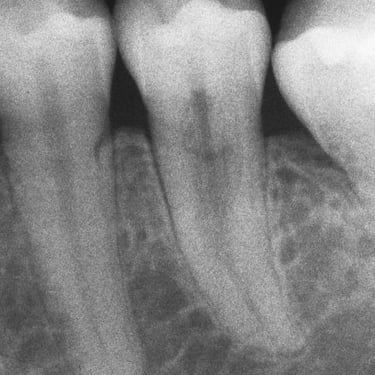

Reabsorción Externa

La reabsorción externa es la pérdida de tejido dental desde el exterior del diente hacia adentro, a menudo como resultado de un trauma o infección.

Los pacientes pueden no tener síntomas hasta que el diente se afloje.

El tratamiento incluye la eliminación de la causa y, a veces, un tratamiento de conducto. En casos severos, puede ser necesario extraer el diente.